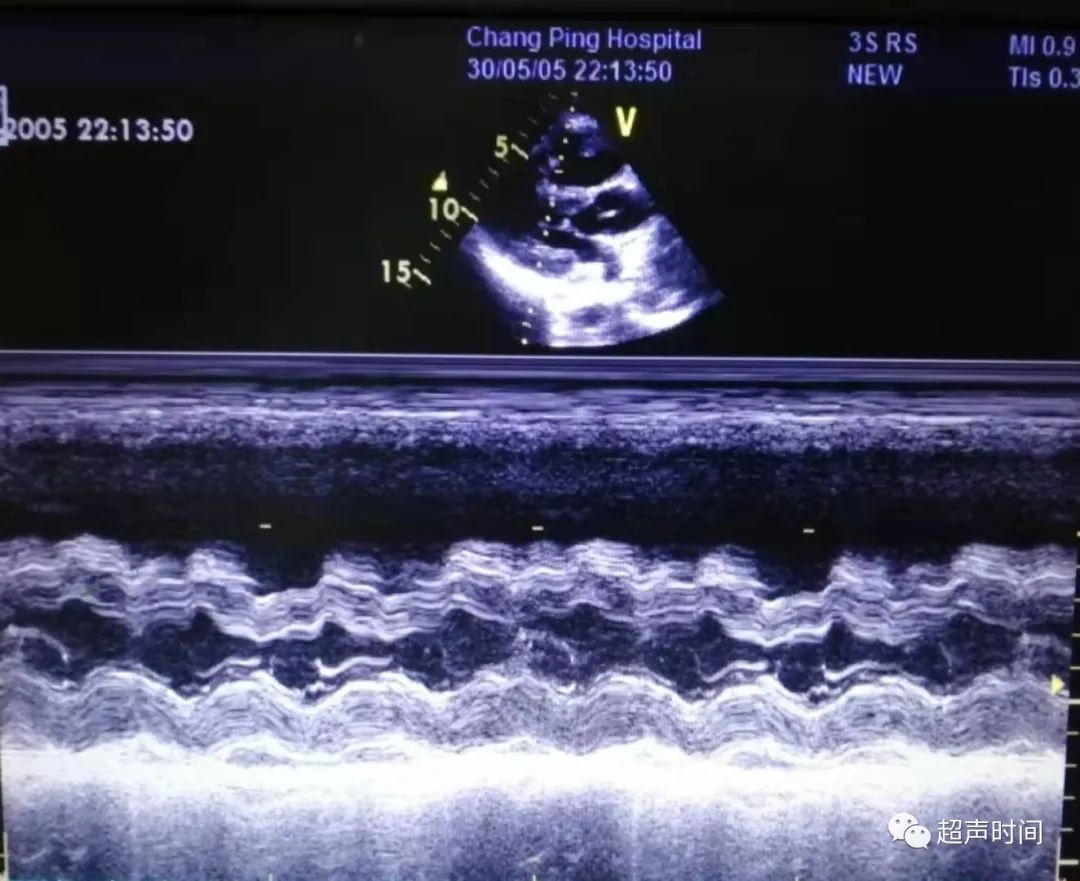

急诊床旁心脏超声所见如下:

图 1 和图 2 左室长轴切面示右室显著增大,其前壁运动减弱、消失,室间隔呈矛盾运动,左室收缩功能正常